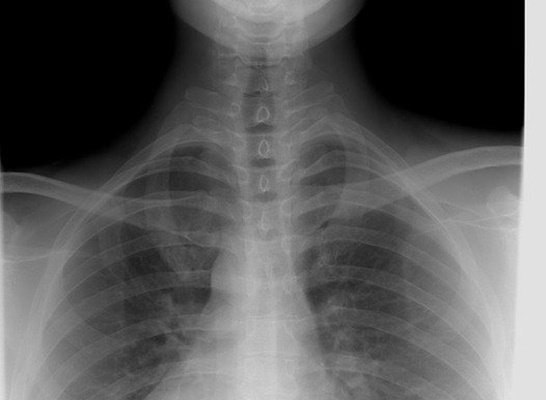

사람이 건강을 유지하며 살아가기 위해서는 심장을 통한 혈액 공급이 원활하게 이루어져야만 합니다. 하지만 심장과 연결되는 혈관이 좁아지거나 막혀서 혈액 순환이 원활하게 되지 않으면 심근경색이 발병하게 되는데요.

심근경색의 주된 원인으로는 인스턴트 음식과 패스트푸드 음식을 주로 섭취하는 식습관의 변화와 비만, 과도한 스트레스입니다.

이러한 원인으로 발생되는 심근경색은 초기증상 발현시에 무조건 신속하게 치료를 시작하는 것이 좋고 특히나 겨울철에는 낮아진 온도에 따라서 혈관이 수축되어 심근경색 증상이 더 심각하게 발현되어 급사를 할 수 있으니 더더욱이 빠르게 병원 검진을 받아야 합니다.